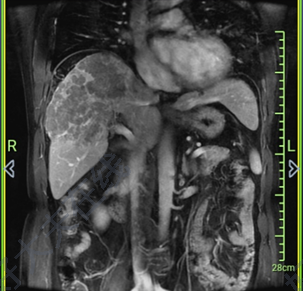

治療前 發(fā)現(xiàn)胃癌肝轉(zhuǎn)移,行胃癌根治性切除和肝轉(zhuǎn)移瘤切除術(shù),病理提示胃竇肝樣腺癌,伴甲胎蛋白升高 治療中 予SOX方案化療6周期,之后替吉奧口服維持治療,7周期后肝內(nèi)復(fù)發(fā),換用阿帕替尼口服,病情進(jìn)展,甲胎蛋白進(jìn)行性升高 治療后 治療后1825天 仍治愈中~~ 治療后180天 完善了基因檢測,提示腫瘤突變負(fù)荷很高,換用PD-1免疫治療8周期,復(fù)查達(dá)到部分緩解,之后停止治療,腫瘤仍進(jìn)行性縮小,直至消失,達(dá)到治愈